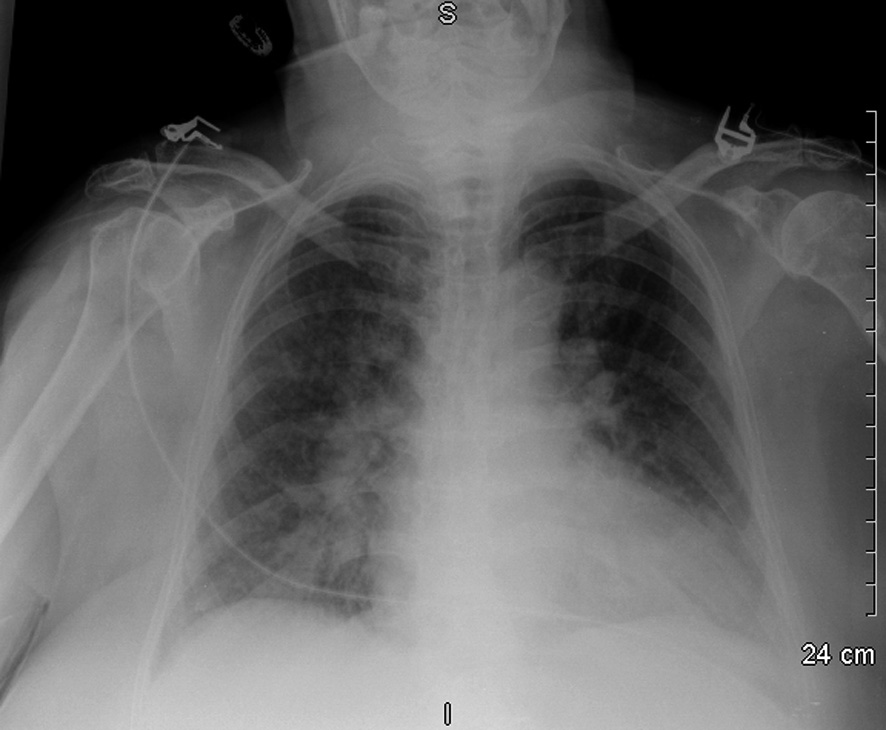

Figure 19 : Radiographie du thorax d’une patiente de 77 ans présentant un œdème aigu du poumon dans les suites d’un infarctus du myocarde de topographie antérieure (traité par angioplastie avec pose d’endoprothèse au niveau du segment proximal de l’artère interventriculaire antérieure)

Noter les opacités alvéolo-interstitielles bilatérales et symétriques prédominant au niveau des hiles pulmonaires dites « opacités en ailes de papillon ».